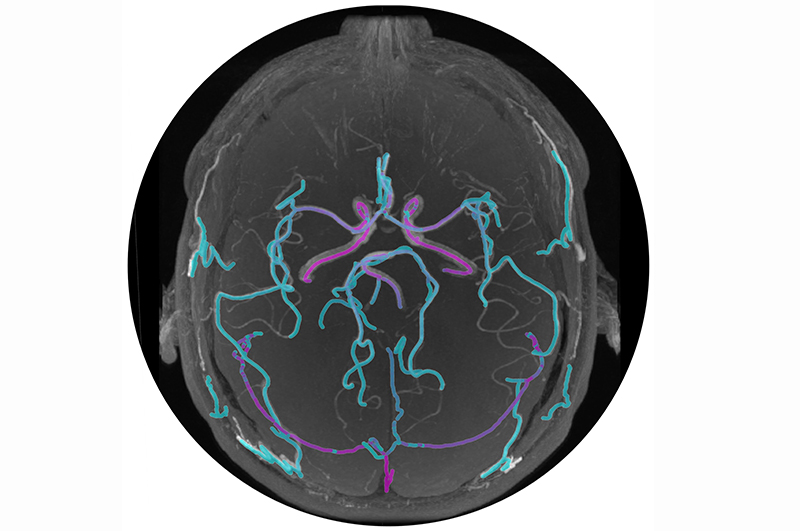

Mātai: New brain blood flow metric offers insights into Alzheimer's

June 2024: Researchers from Mātai Medical Research Institute and Auckland Bioengineering Institute have introduced a groundbreaking metric for analyzing brain blood circulation, as published in Scientific Reports – Nature. Led by first author Sergio Dempsey and co-authors Dr Soroush Safaei, Dr Gonzalo Maso Talou, and Dr Samantha Holdsworth, the team utilized 4D flow MRI technology to develop this innovative approach.

This metric focuses on assessing blood pulsation through brain vessels, akin to wrist pulse with each heartbeat. It evaluates pulse regulation across vessel sizes, crucial for brain oxygen and nutrient distribution. It identifies risks linked to high pulsatility in small brain vessels, crucial in various brain conditions.

"Our findings are a promising step towards better understanding the vascular contributions to neurodegeneration," says Dr Holdsworth, from Mātai and the Faculty of Medical and Health Sciences, University of Auckland.

The study underscores the importance of understanding brain blood pulsatility for clarifying disease mechanisms and exploring new treatments. The team aims to advance clinical strategies to impact patient care and outcomes.

Photo: Mātai Medical Research Institute.